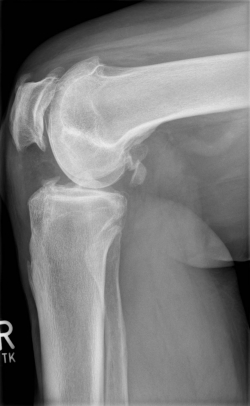

X-rays can be used to reliably diagnose the extent of joint wear. In the case of high-grade gonarthrosis, for example, the joint space and the formation of jagged edges (bone attachments, "osteophytes") as well as axial malalignment can be detected. If additional damage to the internal structures of the knee is suspected, ultrasound examination (sonography) or magnetic resonance imaging (MRI) can help clarify the situation.

Example X-ray images before and after implantation of a Persona knee prosthesis with robot.

a) präoperative Röntgenbilder des kranken Knies in 2 Ebenen | |